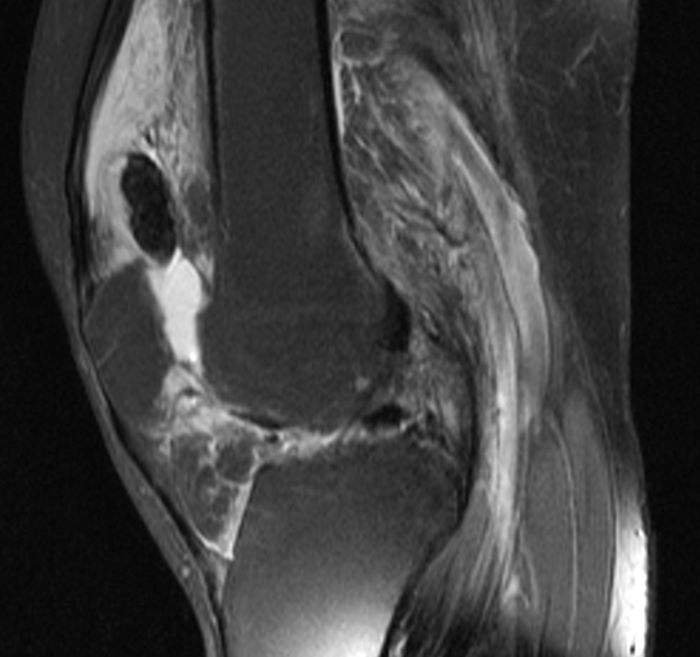

Пигментный виллонодулярный

Пигментный виллонодулярный 113 фотографий